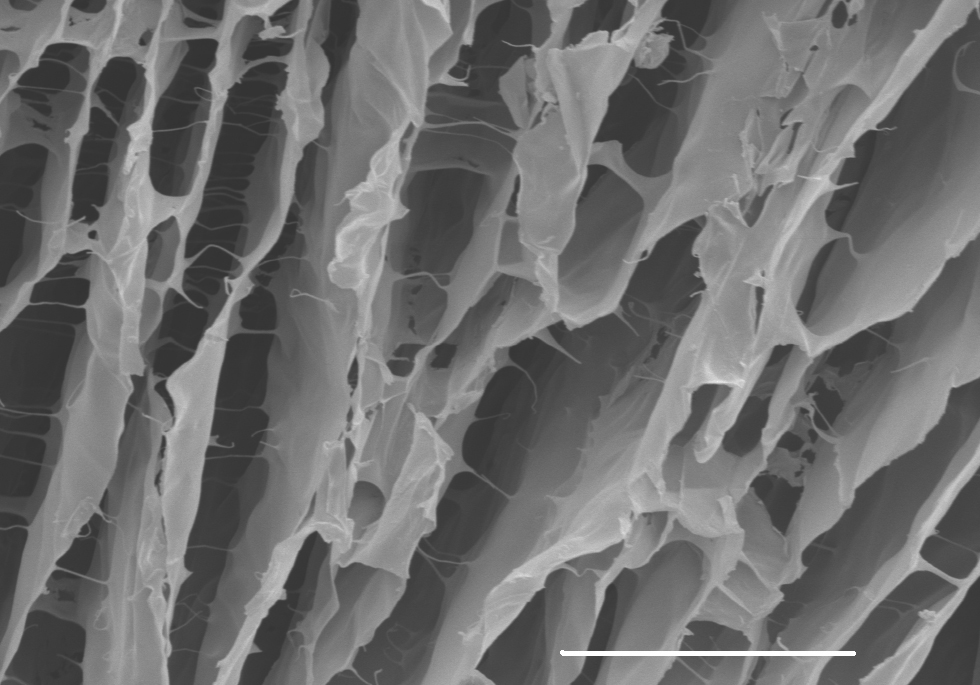

Healing from this type of cancer is a difficult process because of the inevitable damage that is caused to the patient’s vocal cords. The tissues of the vocal cords must be strong enough to withstand the constant movement that occurs while speaking. Dr. Luc Mongeau, the chair of the Department of Mechanical Engineering at McGill University, worked with his team to develop a new injectable hydrogel that can be used for wound repair. A hydrogel is a specific kind of biomaterial that is injected into the body and forms a stable porous structure, which is supported by cross-linking of individual polymer chains. This structure promotes healing by providing room for cells to live and grow in order to repair damaged organs.

Existing hydrogels had an inverse correlation between porosity and toughness, which Mongeau’s team sought to change in order to create a hydrogel with both high porosity and toughness. In order to achieve this, they orchestrated stepwise gelation and phase separation processes. The hydrogels contain porous double networks (PDNs), that are resilient to millions of cycles of mechanical loading. In addition, this material can form interconnected cell-sized pores in situ upon injection. The team tested this material by performing 6,000,000 cycles of high-frequency biomechanical simulations on the PDNs, which it withstood without rupture. The hydrogel also supported cell survival and rapid medium perfusion due to its highly porous matrices. Future direction for the team includes new opportunities for regenerative medicine involving vocal cords, heart, and muscles, and the exciting ability for this type of hydrogel to serve as a biomimetic in vitro 3D cell culture platforms.